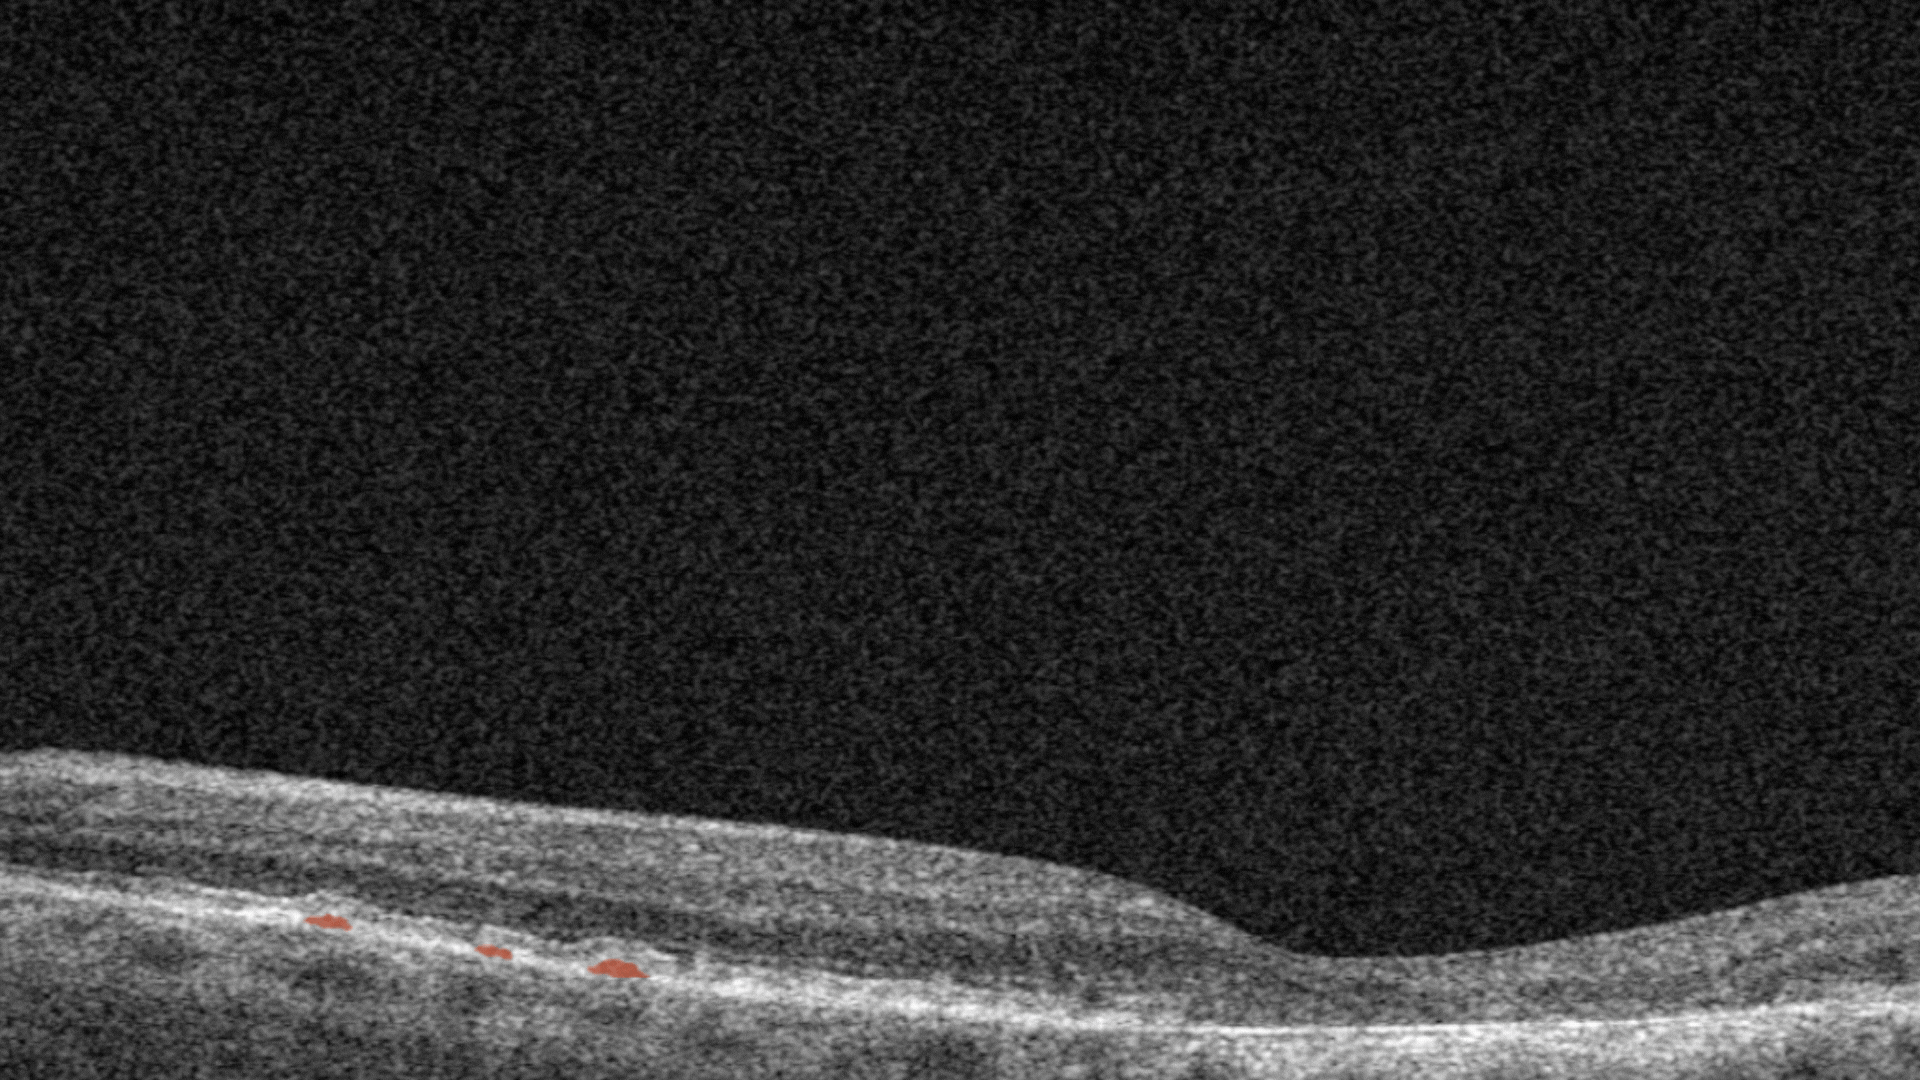

Hard exudates. They are composed of lipid and proteinaceous material, such as fibrinogen and albumin that leak from the impaired blood–retinal barrier.

Intraretinal hyprereflective foci are typically dot-like or round, regular lesions seen in all the retinal layers and choroid